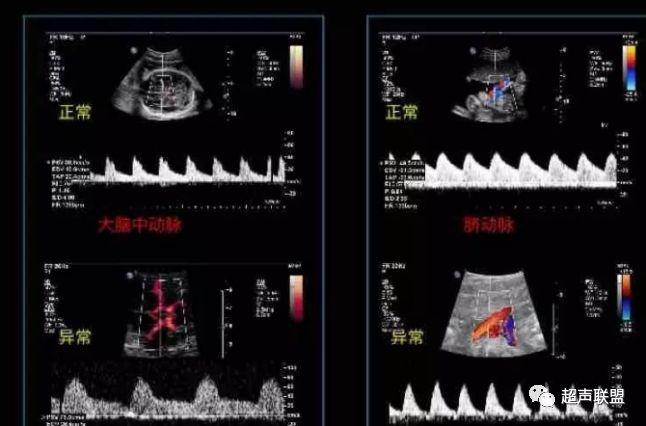

2 胎儿大脑中动脉测定

缺氧早期大脑血液供应增加,颅内血管扩张,阻力降低,舒张末期血流速度增加,PI、RI值下降,说明缺氧早期的血流再分配。当大脑中动脉RI、PI值明显下降,而脐动脉和腹主动脉的PI值升高,大脑中动脉PI值与脐动脉PI值的比值低于2个标准差时,提示严重缺氧的存在。

1、比值标准:大脑中动脉阻力降低,妊娠期,大脑中动脉RI <脐动脉RI;

4、当大脑中动脉RI及PI值明显下降,而脐动脉及腹主动脉的PI值之间升高,大脑中动脉PI值与脐动脉PI值低于两个标准差时,提示为胎儿严重缺氧;

2、大脑中动脉血流阻力降低;

图3 正常大脑中动脉血流频谱

图4 大脑中动脉血流阻力减低